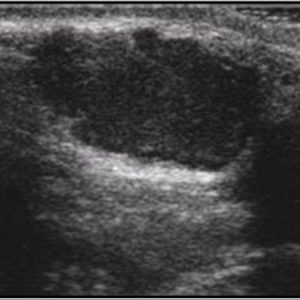

U tuyến nước bọt

Lượt xem: 170» 17-01-2021 -

U tuyến nước bọt

Lượt xem: 174» 17-01-2021 -

U tuyến nước bọt

Lượt xem: 149» 17-01-2021 -

U tuyến nước bọt

Lượt xem: 147» 17-01-2021 -

U tuyến nước bọt

Lượt xem: 146» 17-01-2021 -

U tuyến nước bọt

Lượt xem: 151» 17-01-2021 -

U tuyến nước bọt

Lượt xem: 146» 17-01-2021 -

U tuyến nước bọt

Lượt xem: 136» 17-01-2021 -

U tuyến nước bọt

Lượt xem: 132» 17-01-2021 -

U tuyến nước bọt

Lượt xem: 209» 17-01-2021 -

U tuyến nước bọt

Lượt xem: 150» 17-01-2021 -

U tuyến nước bọt

Lượt xem: 185» 17-01-2021 -

U tuyến nước bọt

Lượt xem: 151» 17-01-2021 -

U tuyến nước bọt

Lượt xem: 212» 17-01-2021 -